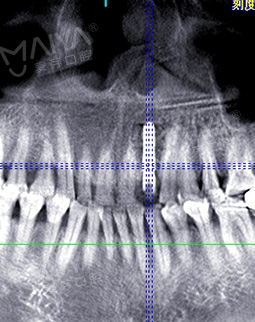

我很信任郑教授带领的种牙团队,而且现在不比当年了,科技也发达了,尤其是麦芽口腔的环境、设备、服务这些都感觉很高大尚,拍个片子都是三维的,不到10分钟,片子就呈现在医生的电脑上了,在几十年前哪有这种设备啊。

郑院长带领的医师团队,给我讲片子很清楚,说我的左上2牙齿出现松动,但是牙龈状况良好,可以告诉我牙齿即拔即种,无需等待3个月拔牙愈合期,避免二次创伤性伤口,他们以修复为导向,尤其我这种前牙的,还要兼顾咀嚼的咬合功能与美观性,虽然不太懂这个技术,但我还是很信赖郑院长的团队的,也感叹现在技术的先进。方案定制完成后,3D口扫取模,就跟牙刷大小一样的东西在口内扫一下,为了制定导板,种牙的时候更方便。